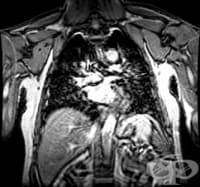

Флебография

Флебографията (от phlebos-вена и graphos-изобразявам) представлява рентгеново изследване на вените с...